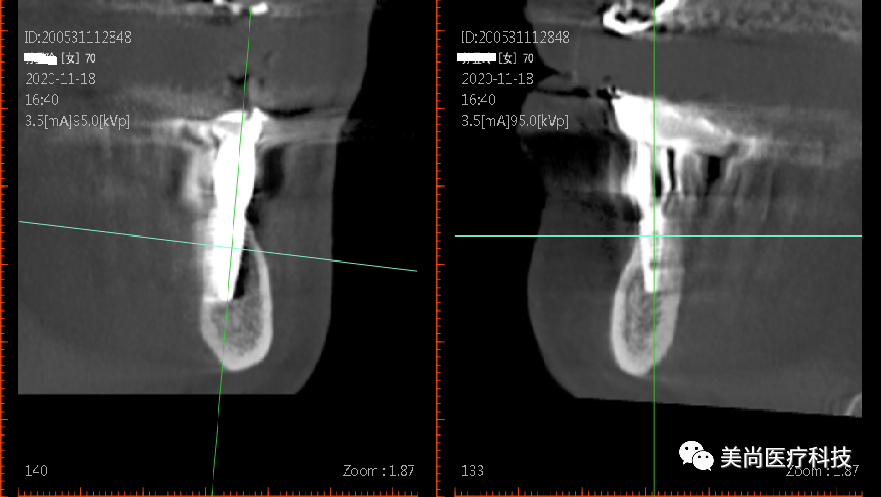

永久修复

戴牙完成

在32、42处植入3.5*10mm植体各一颗,植入扭矩约35n.cm;

在34、44处植入4.0*11.5mm植体各一颗,植入扭矩约40n.cm。